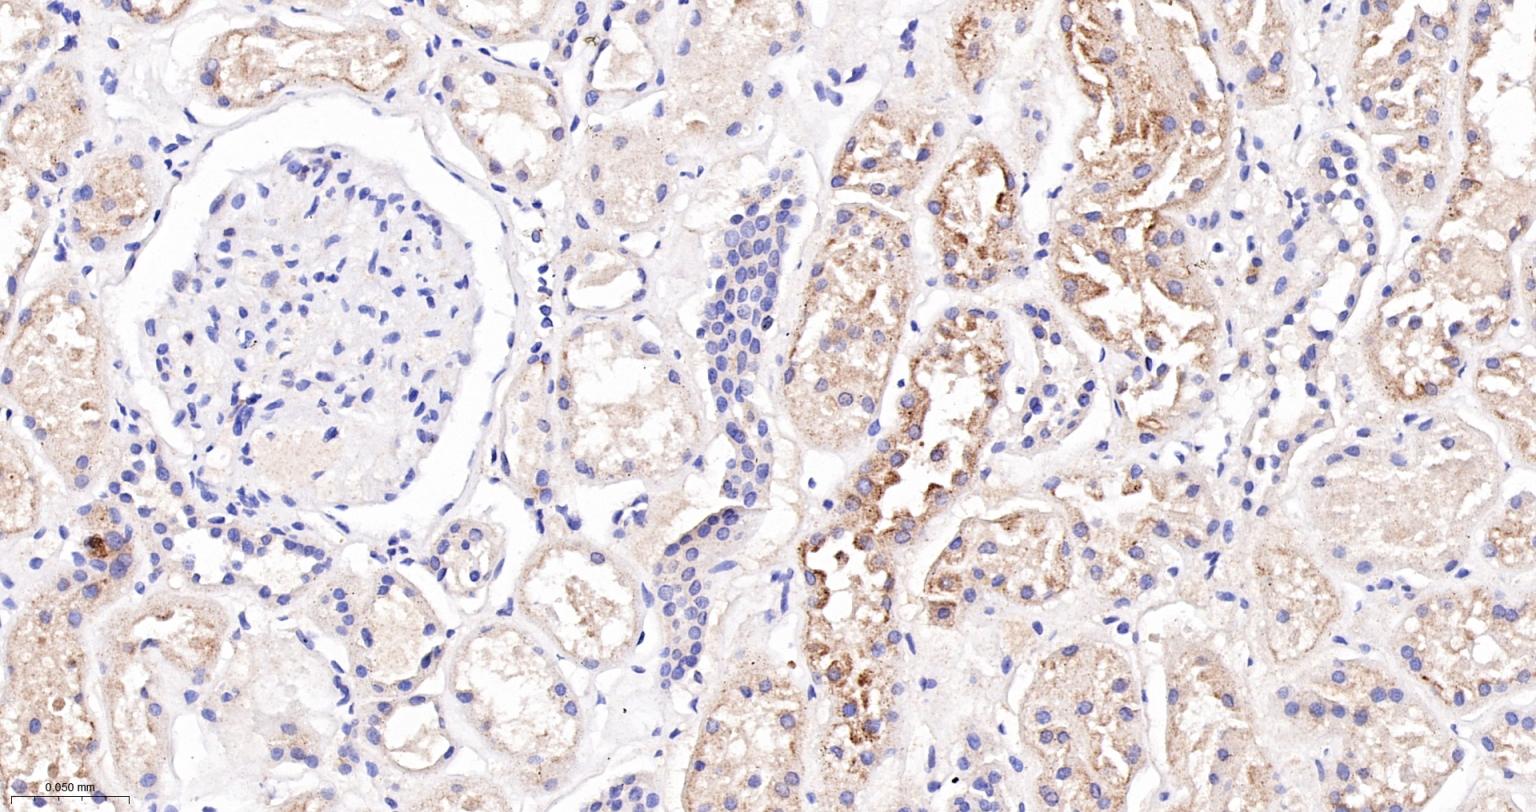

Paraformaldehyde-fixed, paraffin embedded Human Kidney; Antigen retrieval by boiling in sodium citrate buffer (pH6.0) for 15 min; The section was incubated with VAMP8 Monoclonal Antibody, Unconjugated (bsm-61388R) at 1:200 overnight at 4°C, followed by conjugation to the bs-0295G-HRP and DAB (C-0010) staining.